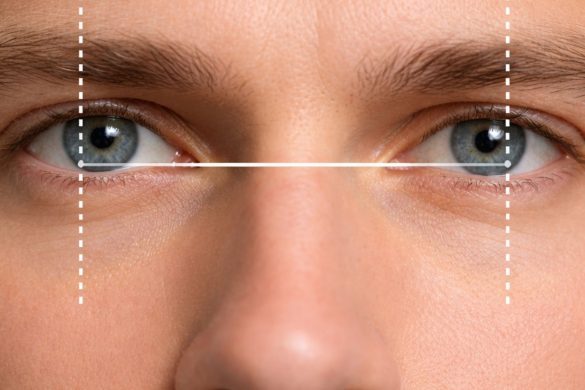

If you have astigmatism, your cornea is shaped like an American football, rather than the typical basketball shape. This irregular curve causes light to focus on multiple points in the eye instead of just one. This then results in blurry or distorted vision at all distances.

Standard contact lenses are spherical. They have the same optical power all the way around. They can rotate freely in the eye without affecting vision. With toric lenses, the lens surface is divided into meridians, which require different optical powers. This is referred to as your “axis.”